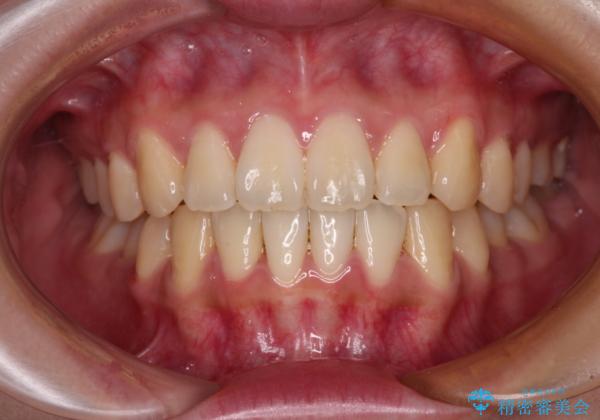

しっかりと装着時間を守ってくださったので、予定通り1年強で治療を終えることができました。